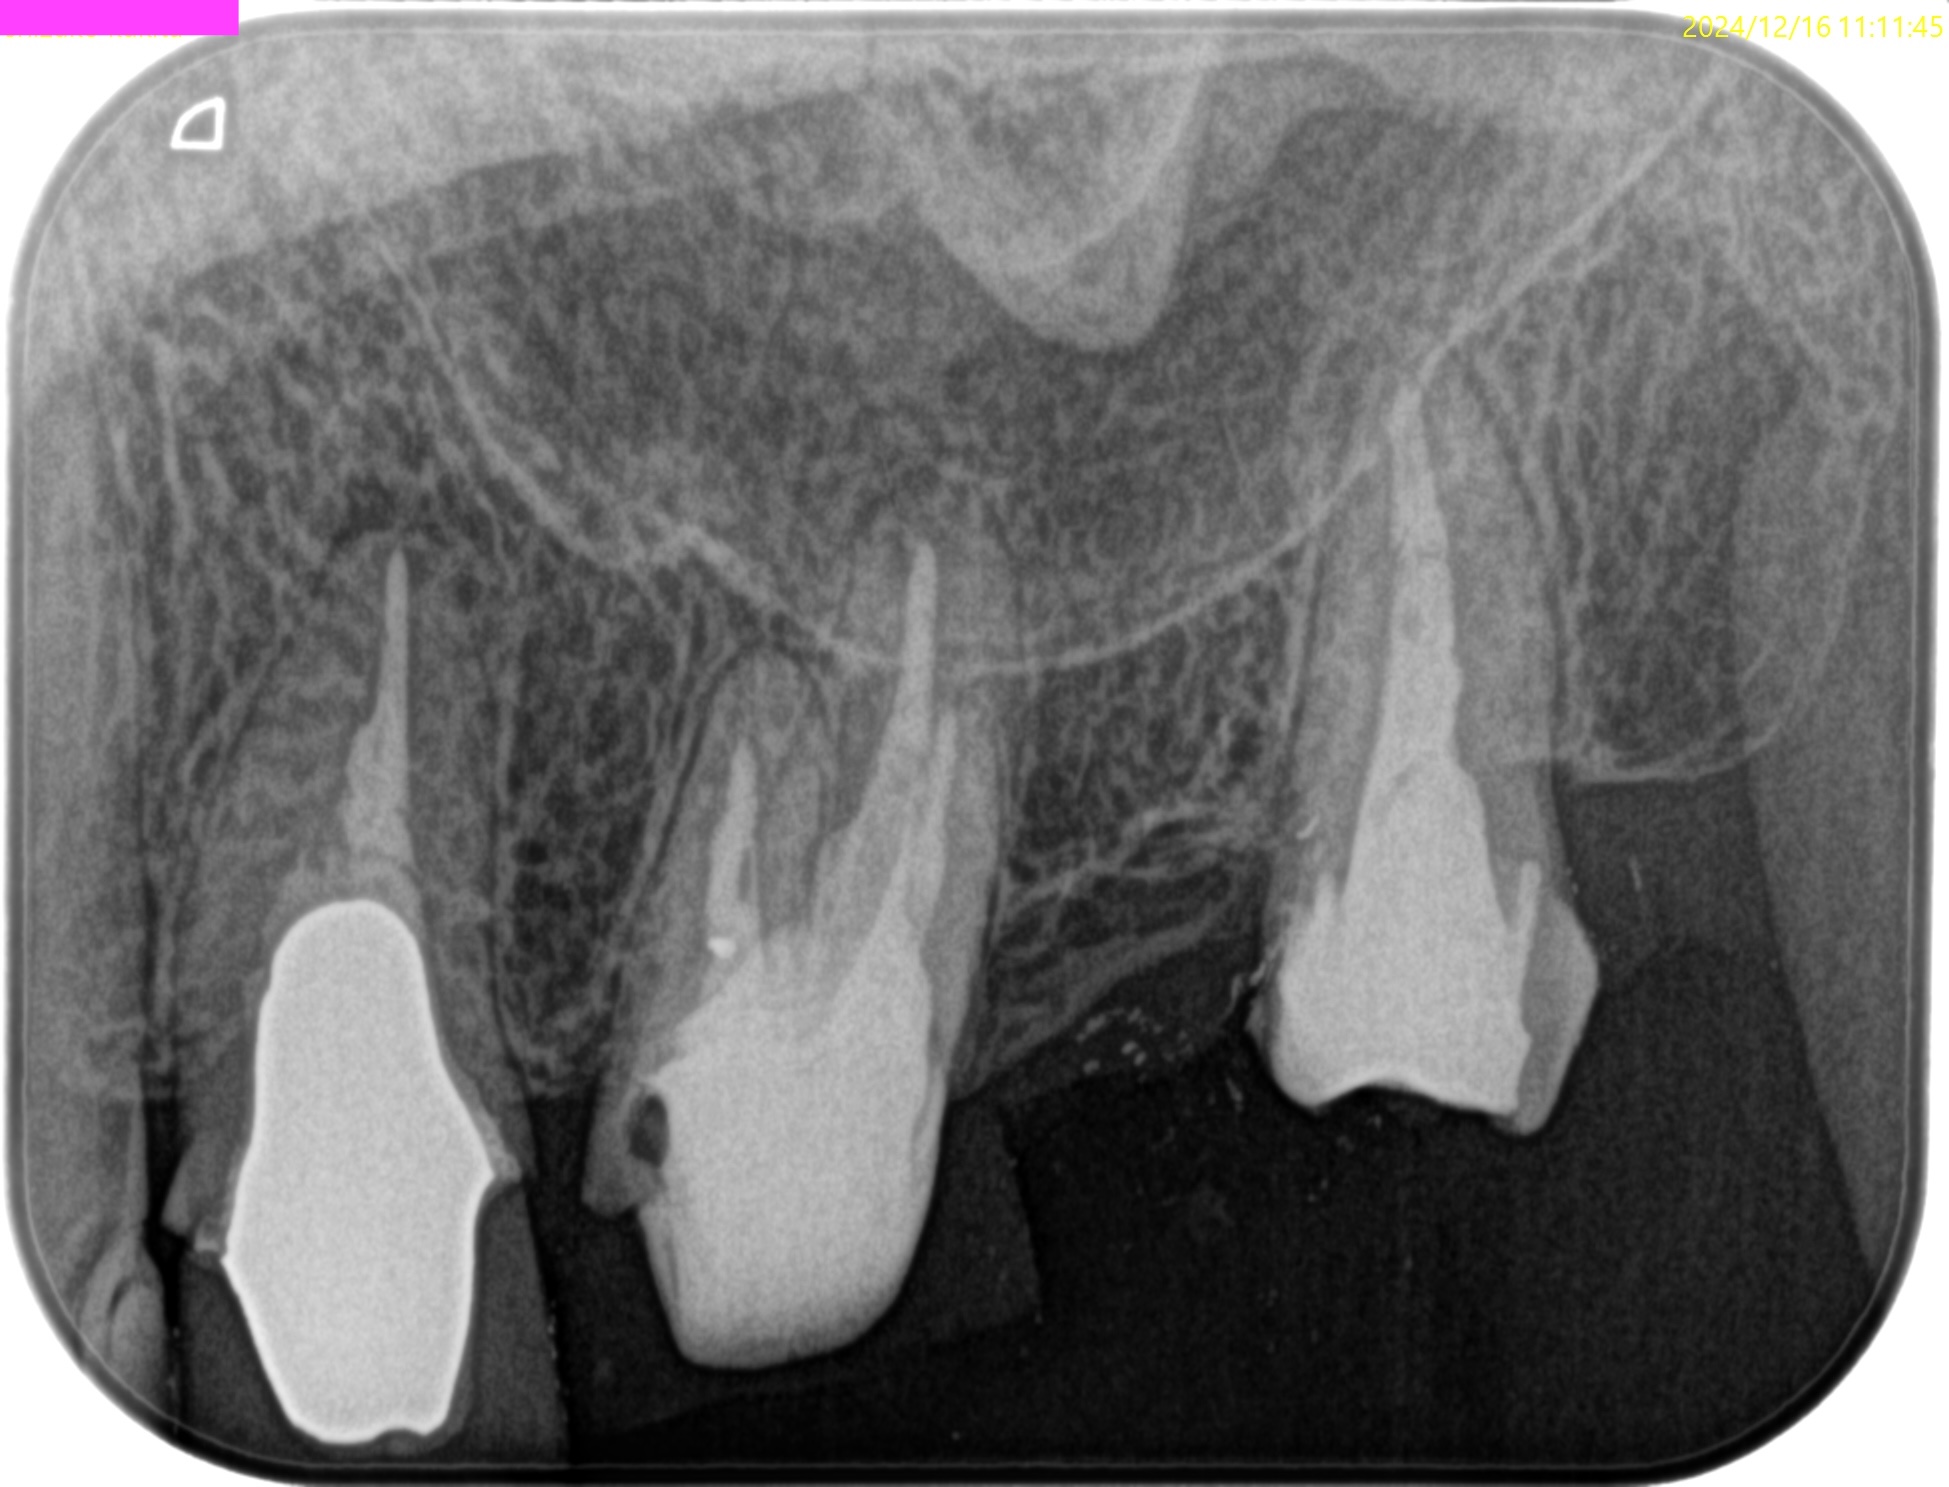

PA(2024.7.1)

CBCT(2024.7.1)

#3

MB

DB

P

MB,DB,Pと3根全てに病変がある。

しかも形成が不完全だ。

再根管治療が濃厚である。

#14

MB,DBには病変がないが、Pに存在する。

これは頭が痛い。

パラタルフラップも困難なケースだからだ。

#16